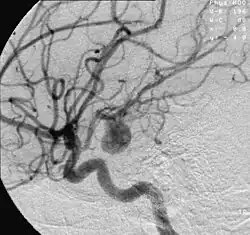

O exame padrão ouro para detecção de aneurisma cerebral não é a tomografia ou a ressonância magnética, e sim o cateterismo cerebral de 4 vasos, denominado angiografia cerebral. Entretanto, não costuma ser o primeiro exame realizado.

O tratamento por embolização dos aneurismas cerebrais começa com a inserção de um cateter (pequeno tubo plástico) na raiz da coxa, na artéria femoral na perna do paciente e navegação dele pelos vasos arteriais, passando pela pelva, abdômen, tórax, pescoço e base do crânio até o aneurisma. Através desta viagem pelo corpo, retificadas pelo cateter, pequenas molas ou espirais de platina são inseridas aos poucos dentro do aneurisma. O processo é assistido por meio de imagens radiológicas, visualizadas em um monitor de vídeo. Ao serem destacadas do cateter são desdobradas dentro da luz no aneurisma, ocupando aos poucos o interior, interferindo no fluxo de sangue para o interior do aneurisma, causando coagulação da luz, redução da pressão interna provocada pela pressão sanguínea e prevenindo sua ruptura. As molas são feitas de platina para que eles possam ser visíveis pelo raio x e bastante flexíveis para conformar-se com a forma de aneurisma e tentar evitar que ele se rompa. Um grande número de pacientes no mundo inteiro já foram tratados com molas de platina destacáveis. As micro-molas mais utilizadas para a embolização do aneurisma são as molas destacáveis de Guglielmi.

Os médicos, preferencialmente neurorradiologistas experientes em intervenções por angiografia encefálica, usam a tecnologia de raios-X em tempo real, chamada visualização fluoroscópica (radioscopia), para visualizar o interior dos vasos sanguíneos. As características externas do aneurisma apenas podem ser visibilizadas pela cirurgia aberta.